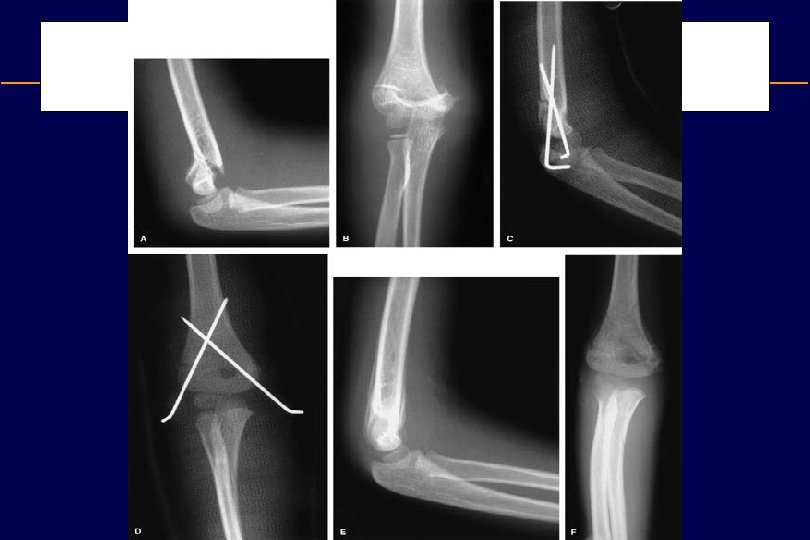

Supracondylar fractures • These fractures occur most commonly in children between the ages of 6 -9 years. • These fractures may lead to vascular and neurological complications

Radial Head Fracture • Radial head fractures are generally caused by longitudinal loading from a fall on an outstretched hand or dislocation of the elbow.

Olecranon Fractures • Fracture of the olecranon commonly occur with a direct blow or as an avulsion injury with triceps contracture • The fractures generally are transverse or oblique in orientation and enter the trochlear notch.